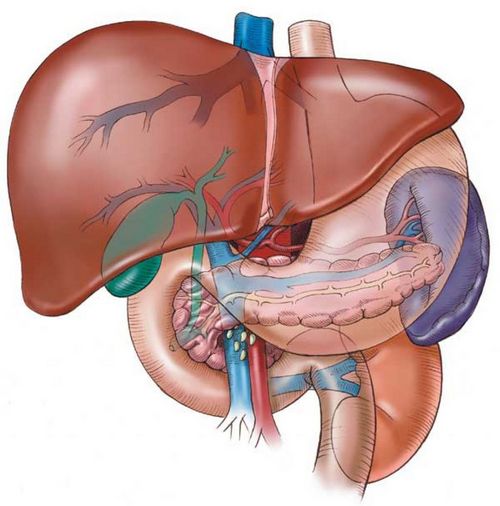

Що робити при перших ознаках набряклості? Необхідно звернути пильну увагу на стан нирок, печінки і серцево-судинної системи вагітної жінки. Найчастіше саме ці життєво важливі органи не витримують додаткового навантаження і дають збій.

Якщо ж до цього у майбутньої мами підвищується артеріальний тиск і з'являється білок в аналізах сечі, це означає, що нирки не справляються з роботою за двох.